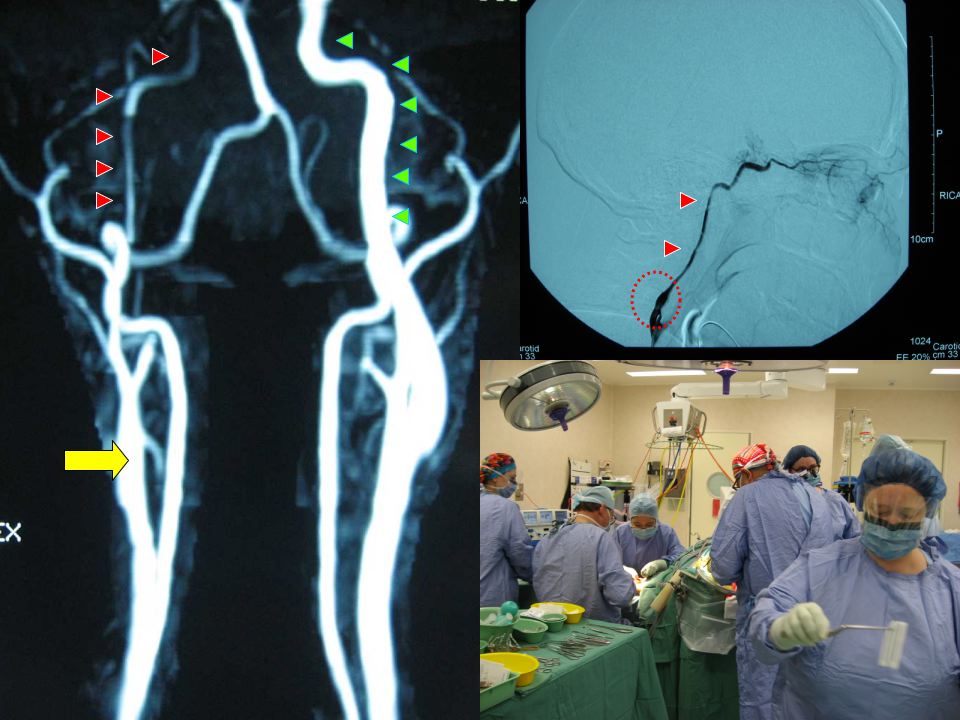

Si chiama “anastomosi non occlusiva assistita da laser ad eccimeri” (ELANA) la tecnica utilizzata dai neurochirurghi di Mestre per eseguire un by-pass tra l’arteria carotide al collo e l’arteria cerebrale media nel cervello. L’intervento è stato per la prima volta in Italia eseguito su una giovane signora portatrice di un tumore cerebrale benigno (meningioma) che aveva in gran parte occluso l’arteria carotide all’interno del cranio. Il Dottor Giuseppe Trincia, Direttore di Neurochirurgia e del Dipartimento di Scienze Neurologiche dell’ULSS Veneziana ci spiega: “si trattava di un voluminoso meningioma sviluppatosi alla base del cranio che comprimeva i nervi ottici e che non poteva essere rimosso completamente senza lesionare la carotide intracranica con gravi rischi di ischemia cerebrale. Era quindi necessario creare una nuova circolazione per quell’emisfero cerebrale, cioè un by-pass extra-intracranico”. L’unica possibilità era di applicare una tecnica innovativa, messa a punto dal Prof. Tulleken, neurochirurgo di Utrecht in Olanda, eseguita solo in selezionati Centri europei e nordamericani. Questa tecnica richiede l’utilizzo di un particolare laser “a freddo”, apparecchiatura ad alta tecnologia, presente in pochissimi Ospedali, acquistata due anni fa a Mestre e utilizzata per procedure di Cardiologia e Chirurgia Vascolare. Un neurochirurgo di Mestre, il dott. Carlo Conti, responsabile dell’Unità Operativa Semplice di Neurochirurgia Vascolare, aveva seguito il training sia “in vitro” che “in vivo” presso l’Università di Utrecht.

“A Mestre, con questa tecnica – continua il Dott. Trincia – avevamo recentemente operato (primi nel Nord Italia) 3 pazienti con aneurisma cerebrale altrimenti intrattabile, con buoni risultati, e questo ci ha permesso di applicare la tecnica anche in questa paziente. L’intervento è durato quasi 10 ore e ha richiesto la collaborazione di Neurologi, Neuroradiologi, Chirurghi Vascolari, Anestesisti, oltre a tutto il personale di Sala Operatoria. Il Prof. Tulleken stesso, presente all’intervento con i tecnici del laser, ha avuto modo di apprezzare questa interdisciplinarietà e, sia per l’affidabilità, che per la qualità delle procedure ha inserito Mestre (unico Ospedale del Nord Italia) tra i Centri mondiali di riferimento della tecnica ELANA”. La paziente ha avuto un decorso postoperatorio estremamente favorevole ed il controllo ha dimostrato il perfetto funzionamento del by-pass. A questo punto sarà possibile rimuovere il meningioma sacrificando l’arteria carotide senza alcuna compromissione della circolazione cerebrale.

Una tecnica recentemente introdotta dal gruppo di Neurochirurghi olandesi dell’Università di Utrecht permette di trattare pazienti fino ad ora giudicati inoperabili. Con tale tecnica (che recentemente è stata adottata anche dai Neurochirurghi di Mestre) sono stati trattati più di 100 pazienti in pochissimi centri europei e nordamericani ed i risultati clinici sono soddisfacenti. Si tratta della Excimer Laser Assisted Non-occlusive Anastomosis (ELANA) cioè di un by-pass (utilizzando in genere una vena prelevata dal paziente stesso) tra un’arteria “a monte” della malattia ed un’altra arteria “a valle” all’interno del cervello (vedi disegno); tale rivascolarizzazione è definita “non-occlusiva” in quanto permette di eseguire il by-pass sull’arteria cerebrale senza occluderla e quindi riducendo i rischi di ischemia cerebrale. Per tale procedura è necessaria un’apparecchiatura laser ad eccimeri, “a freddo”, unica nel suo genere.